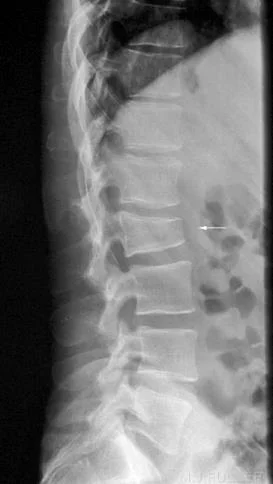

- Fall from height on feet

- fractured calcaneus and lumbar spine

- Two injuries

- e.g. calcaneal fractures & spine injuries

Advanced Imaging

- CT Scan:

- In complex and intra-articular fractures

- In spine

- In calcaneal fractures